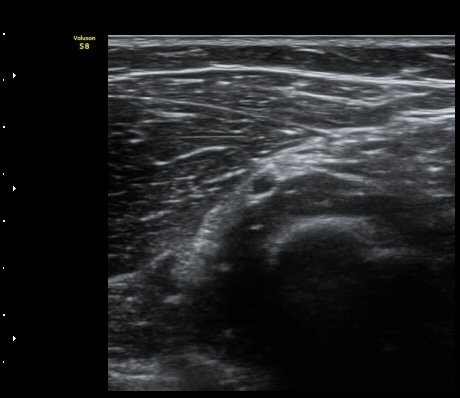

ÃÊÀ½ÆÄ °Ë»ç